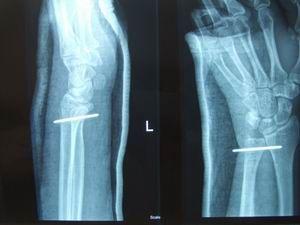

下尺桡关节位置图,桡尺关节位置图

下尺桡关节脱位的诊断和治疗

由 a data-lemmaid="1657254">桡骨 /a>下端腕关节面和尺骨下方的关节

下尺桡关节损伤

少见下尺桡关节掌侧脱位二例

下尺桡关节脱位

下尺桡关节半脱位

下尺桡关节

下尺桡关节分离